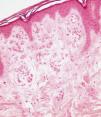

Presentamos una mujer de 40 años con antecedentes de obesidad, hipertensión y migraña, en tratamiento con clortalidona, propanolol y rizatriptan, que consultó porque desde hacía años presentaba una mácula acrómica de límites netos y distribución lineal en la cara externa del muslo y la pierna izquierdos, que dibujaba el trayecto de una variz (fig. 1). Esta lesión apareció sobre un área de piel previamente sana. No existían otras lesiones características de vitíligo, si bien refería el antecedente de esta enfermedad en su abuela materna. El estudio analítico, que incluyó hemograma, bioquímica general y parámetros de autoinmunidad (ANA, anticuerpos antitiroideos) resultó normal. El estudio histopatológico de la lesión mostró una epidermis normal, con presencia de ectasias vasculares en la dermis superficial y ausencia de melanófagos o inflamación (fig. 2). La tinción de Masson-Fontana permitió comprobar la ausencia de melanocitos en la capa basal (fig. 3). Las características clínicas e histológicas fueron coherentes con el diagnóstico de vitíligo. Tras diez meses de seguimiento sin tratamiento alguno se apreció repigmentación de las áreas acrómicas con un patrón perifolicular, hallazgo que reforzó el diagnóstico.